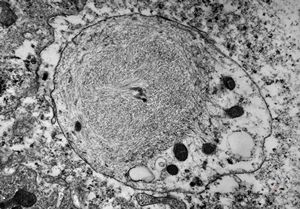

F,50y. | progressive multifocal leukoencephalopathy- viral particles in a glial cell

F,50y. | progressive multifocal leukoencephalopathy- viral particles in a glial cell

F,50y. | progressive multifocal leukoencephalopathy- viral particles in a glial cell